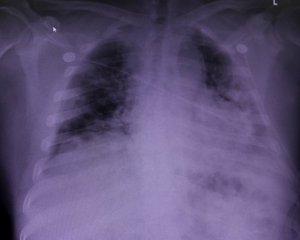

Інфекція повністю знищила їхні дихальні шляхи, тож пересадження стало єдиним шансом на виживання, пише ТСН.

Це 28-річна юристка Майра та 62-річний автомеханік Браян. Обоє щасливчиків почуваються добре, а органи прижилися.

Лікарі зазначили, що без цієї операції обоє пацієнтів вижити не змогли б. Наразі за ними уважно спостерігають медики, прогнози на одужання в обох добрі.